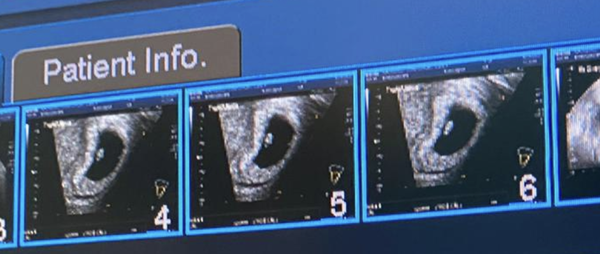

Baba is all okay and measuring correctly! I've got a cyst on my right ovary so that's what's been causing the cramping! So relieved ♥️

@Casper94 so glad all is well and there’s a simple explanation for the cramping! How lovely to see baby.